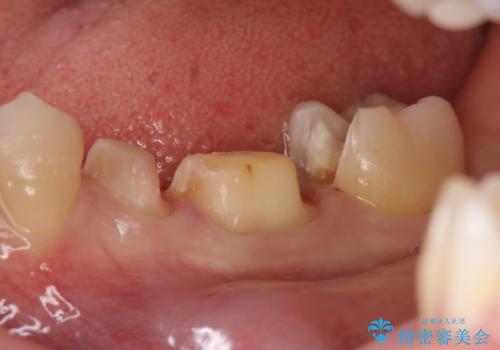

- 左下奥歯の銀歯が気になると来院された方の症例です。

左下7はセラミックインレーによる修復を行い、左下5、6はオールセラミッククラウンによる補綴を行いました。